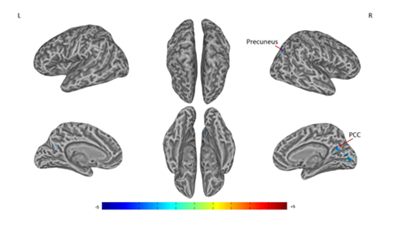

A significant difference of alterations in right SI connectivity between two study groups was observed in right PCC and right precuneus (Figures 3 & Table 3). For the alterations in left SI connectivity, the difference was observed in right MTG, secondary somatosensory cortex (SII), ACC, left MTG, cuneus (Figures 4 & Table 4).

Figure 3 Connectivity-altered areas with right SI in intergroup analysis.

P ≤ 0.01, α ≤ 0.02, corrected by the Monte Carlo method. PCC, posterior cingulate cortex

Precuneus (39)

R

42

-72

36

-4.41